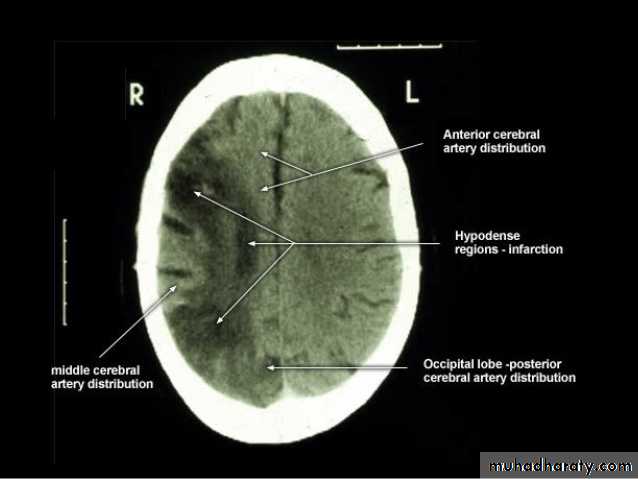

• Role of CT and MR in patients with stroke• Early CT and MR signs of infarction

• Exclude hemorrhage• Differentiate between irreversibly affected brain tissue and reversibly impaired tissue (dead tissue versus tissue at risk)